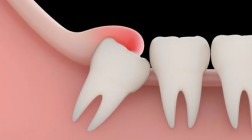

②生长位置不正智齿长歪挤压邻牙或出现阻生智齿。

智齿长歪和相邻的恒牙挤着生长,会不易清洁,当生长空间不足时,还会出现严重的牙龈肿胀,甚至导致前牙歪斜、排列拥挤,牙列不齐阻生智齿(智齿刺客)通常都埋在牙槽骨里面,非常容易被忽略,需要通过拍牙片诊断。